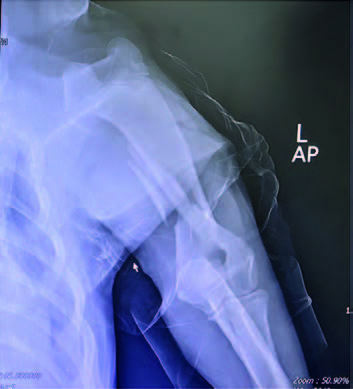

This case study involves a 5-monthsold, intact male Golden Retriever dog presented with tetraparesis, seizure and comatose by a car accident 5 days ago. Physical examination presented unconsciousness, tetraparesis, tachypnea, right temporomandibular joint (TMJ) luxated and crepitus of left humerus. Neurological examination was localized to cerebral cortex and brain stem lesions. The Modified Glasgow Coma Scale (MGCS) was 3. Laboratory tests revealed anemia of 23.1% (reference range, 35-45%), leukocytosis of 19.09 x 103/μL (reference range, 5-14.1 x 103/μL). Radiography was presented to skull fracture, lung hemorrhage (Figure 1) and left humerus fracture (Figure 2).

CT scan of skull is preferred for evaluate bone fractures and identify areas of acute hemorrhage or edema. CT scan showed multiple sites of skull fractures, right maxilla, both frontal, right zygomatic, right caudal mandible, right caudal zygomatic, right temporal, left occipital bone (Figure 3) and patchy small area of hyper-attenuation at the cranial of midbrain in pre-contrast study (Figure 4), no detectable mass effect, hypo-attenuated of large edematous parenchyma in the brain, right temporomandibular joint is displacement (Figure 5) and left tympanic bulla shows partial ventral fluid-filled.

CT skull presented to multiple skull fractures, brain edema, midbrain hemorrhage and right TMJ luxation.